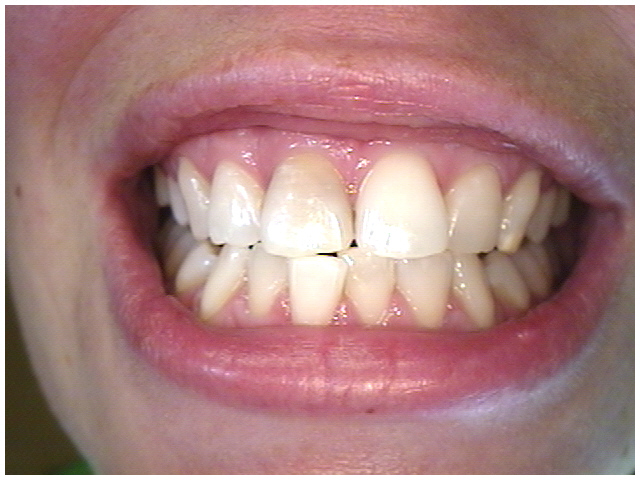

Dark front tooth

Dark front tooth indicating

the tooth is 'dead'